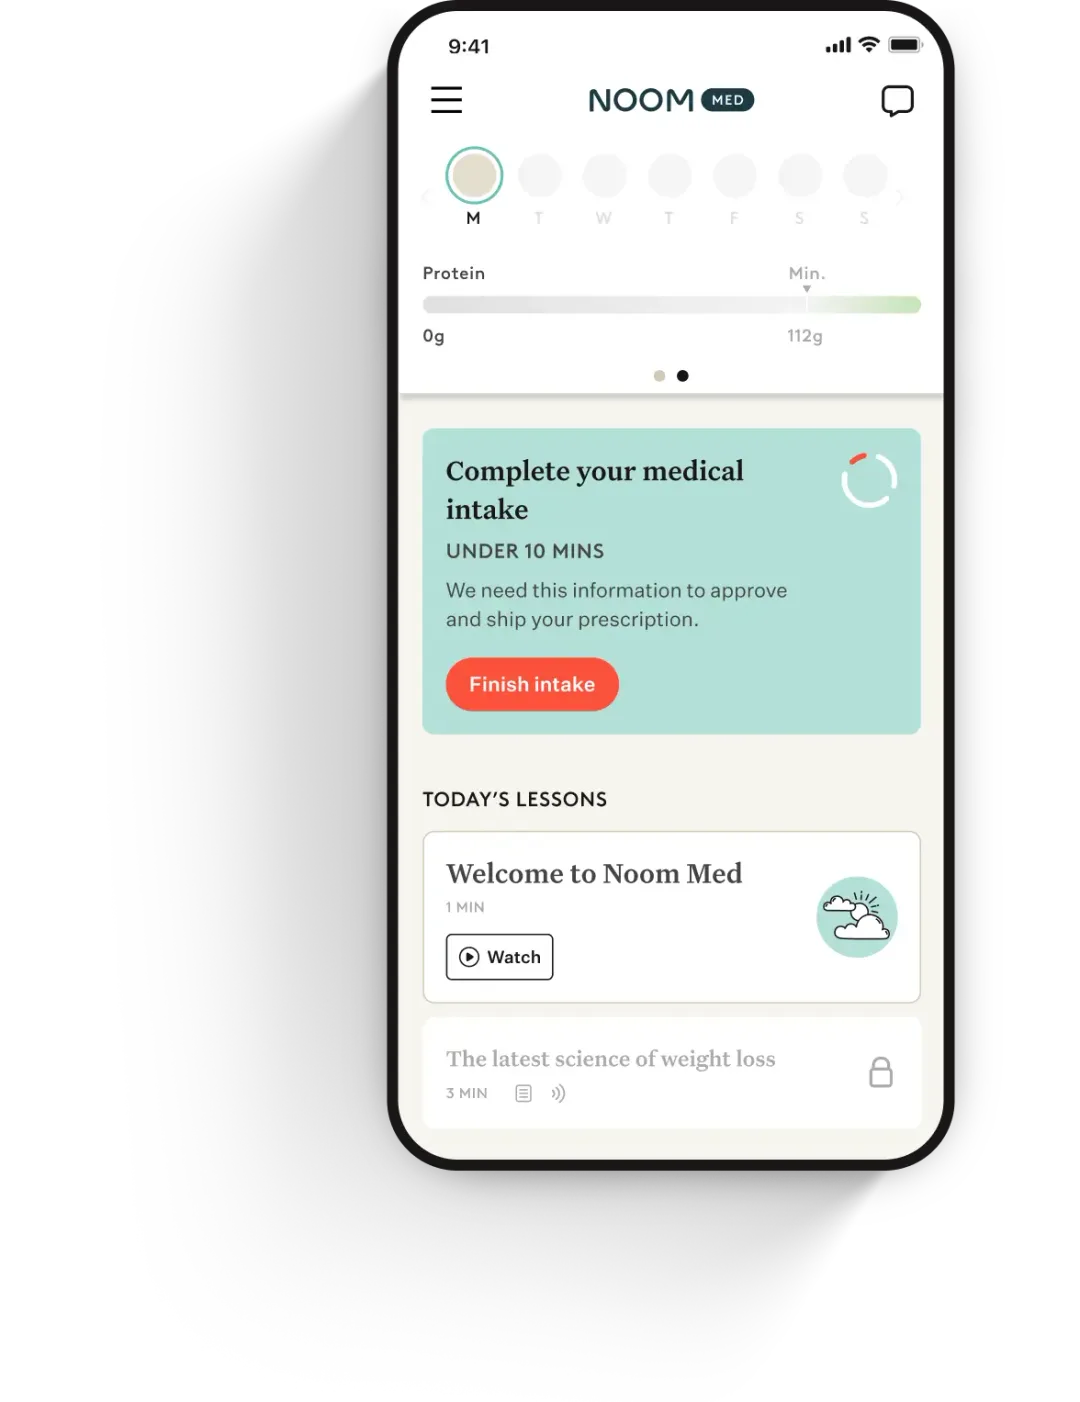

How to access Ozempic® with Noom

STEP 1

Complete a brief intake survey

Share your health history and weight-loss goals to get started.

STEP 2

Understand your health with labs

Take a quick and convenient metabolic lab test to get a picture of your health.

STEP 3

Consult with an expert clinician

A clinician will quickly evaluate your results and provide a prescription all online, if clinically appropriate.

STEP 4

Start losing weight with a customized medication and support program

If prescribed, you’ll get a custom plan designed for your goals and biology.

Ongoing care and medication

Stay on track with unlimited access to your clinician and medication refills, where clinically appropriate.